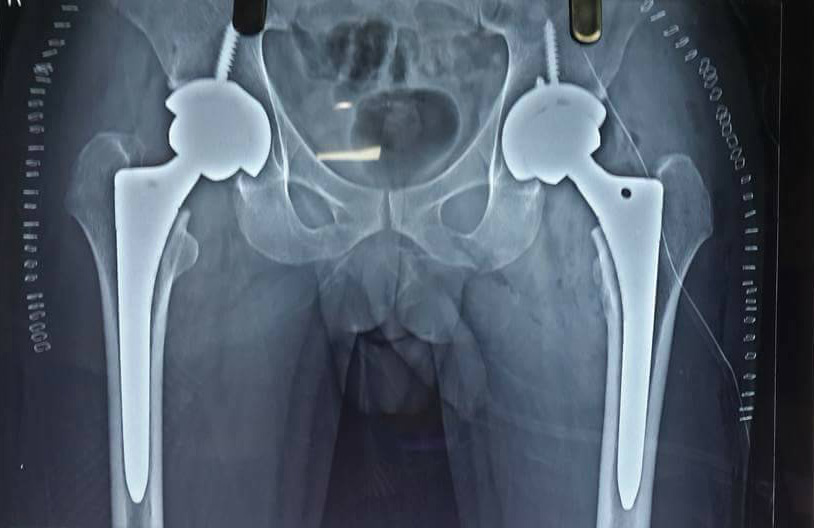

A 55 yrs old male from Dewas suffering for last 10 years from bilateral hip Avascular necrosis, not able to walk at all underwent bilateral total hip replacement (THR) at our centre using latest techniques giving best result to the patient. He started walking the next day. It was a life changing experience for the patient from not able to walk all to walking painlessly.

We are treating hip avascular necrosis and other complex hip disorders on regular basis in central India, Indore. Procedure done by our dedicated Joint Replacement Surgeon Dr Sachin Chhabra from Push Orthopaedic Centre.